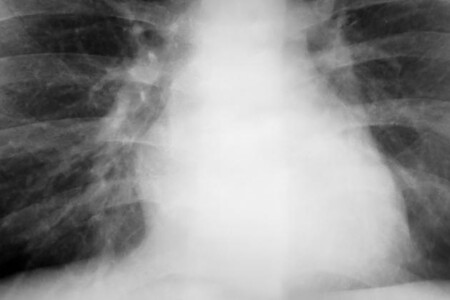

Pleurální výpotek není nemoc sama o sobě, ale představuje častou komplikaci či projev mnoha nemocí, resp. patologických procesů. Mezi nejčastější příčiny pleurálního výpotku patří městnavé srdeční selhání, pneumonie, nádorová onemocnění a plicní embolie. Pleurální výpotek je nebezpečný stav, který může probíhat i skrytě bez příznaků nebo se projevit zhoršujícím se dýcháním a kašlem. Každý takový stav je nutné konzultovat s lékařem a neprodleně začít léčit, aby se předešlo vážným komplikacím ohrožující lidský život.

Otok plic, neboli plicní edém, je označení pro nebezpečný stav, kdy se v plicích objeví tekutina. Díky této tekutině se zjednodušeně řečeno naše plíce topí. Plicní sklípky tak nemohou splňovat svou úlohu výměny plynů, což vede k silnému nedostatku dechu. Jaké jsou příčiny, příznaky a léčba otoku plic?